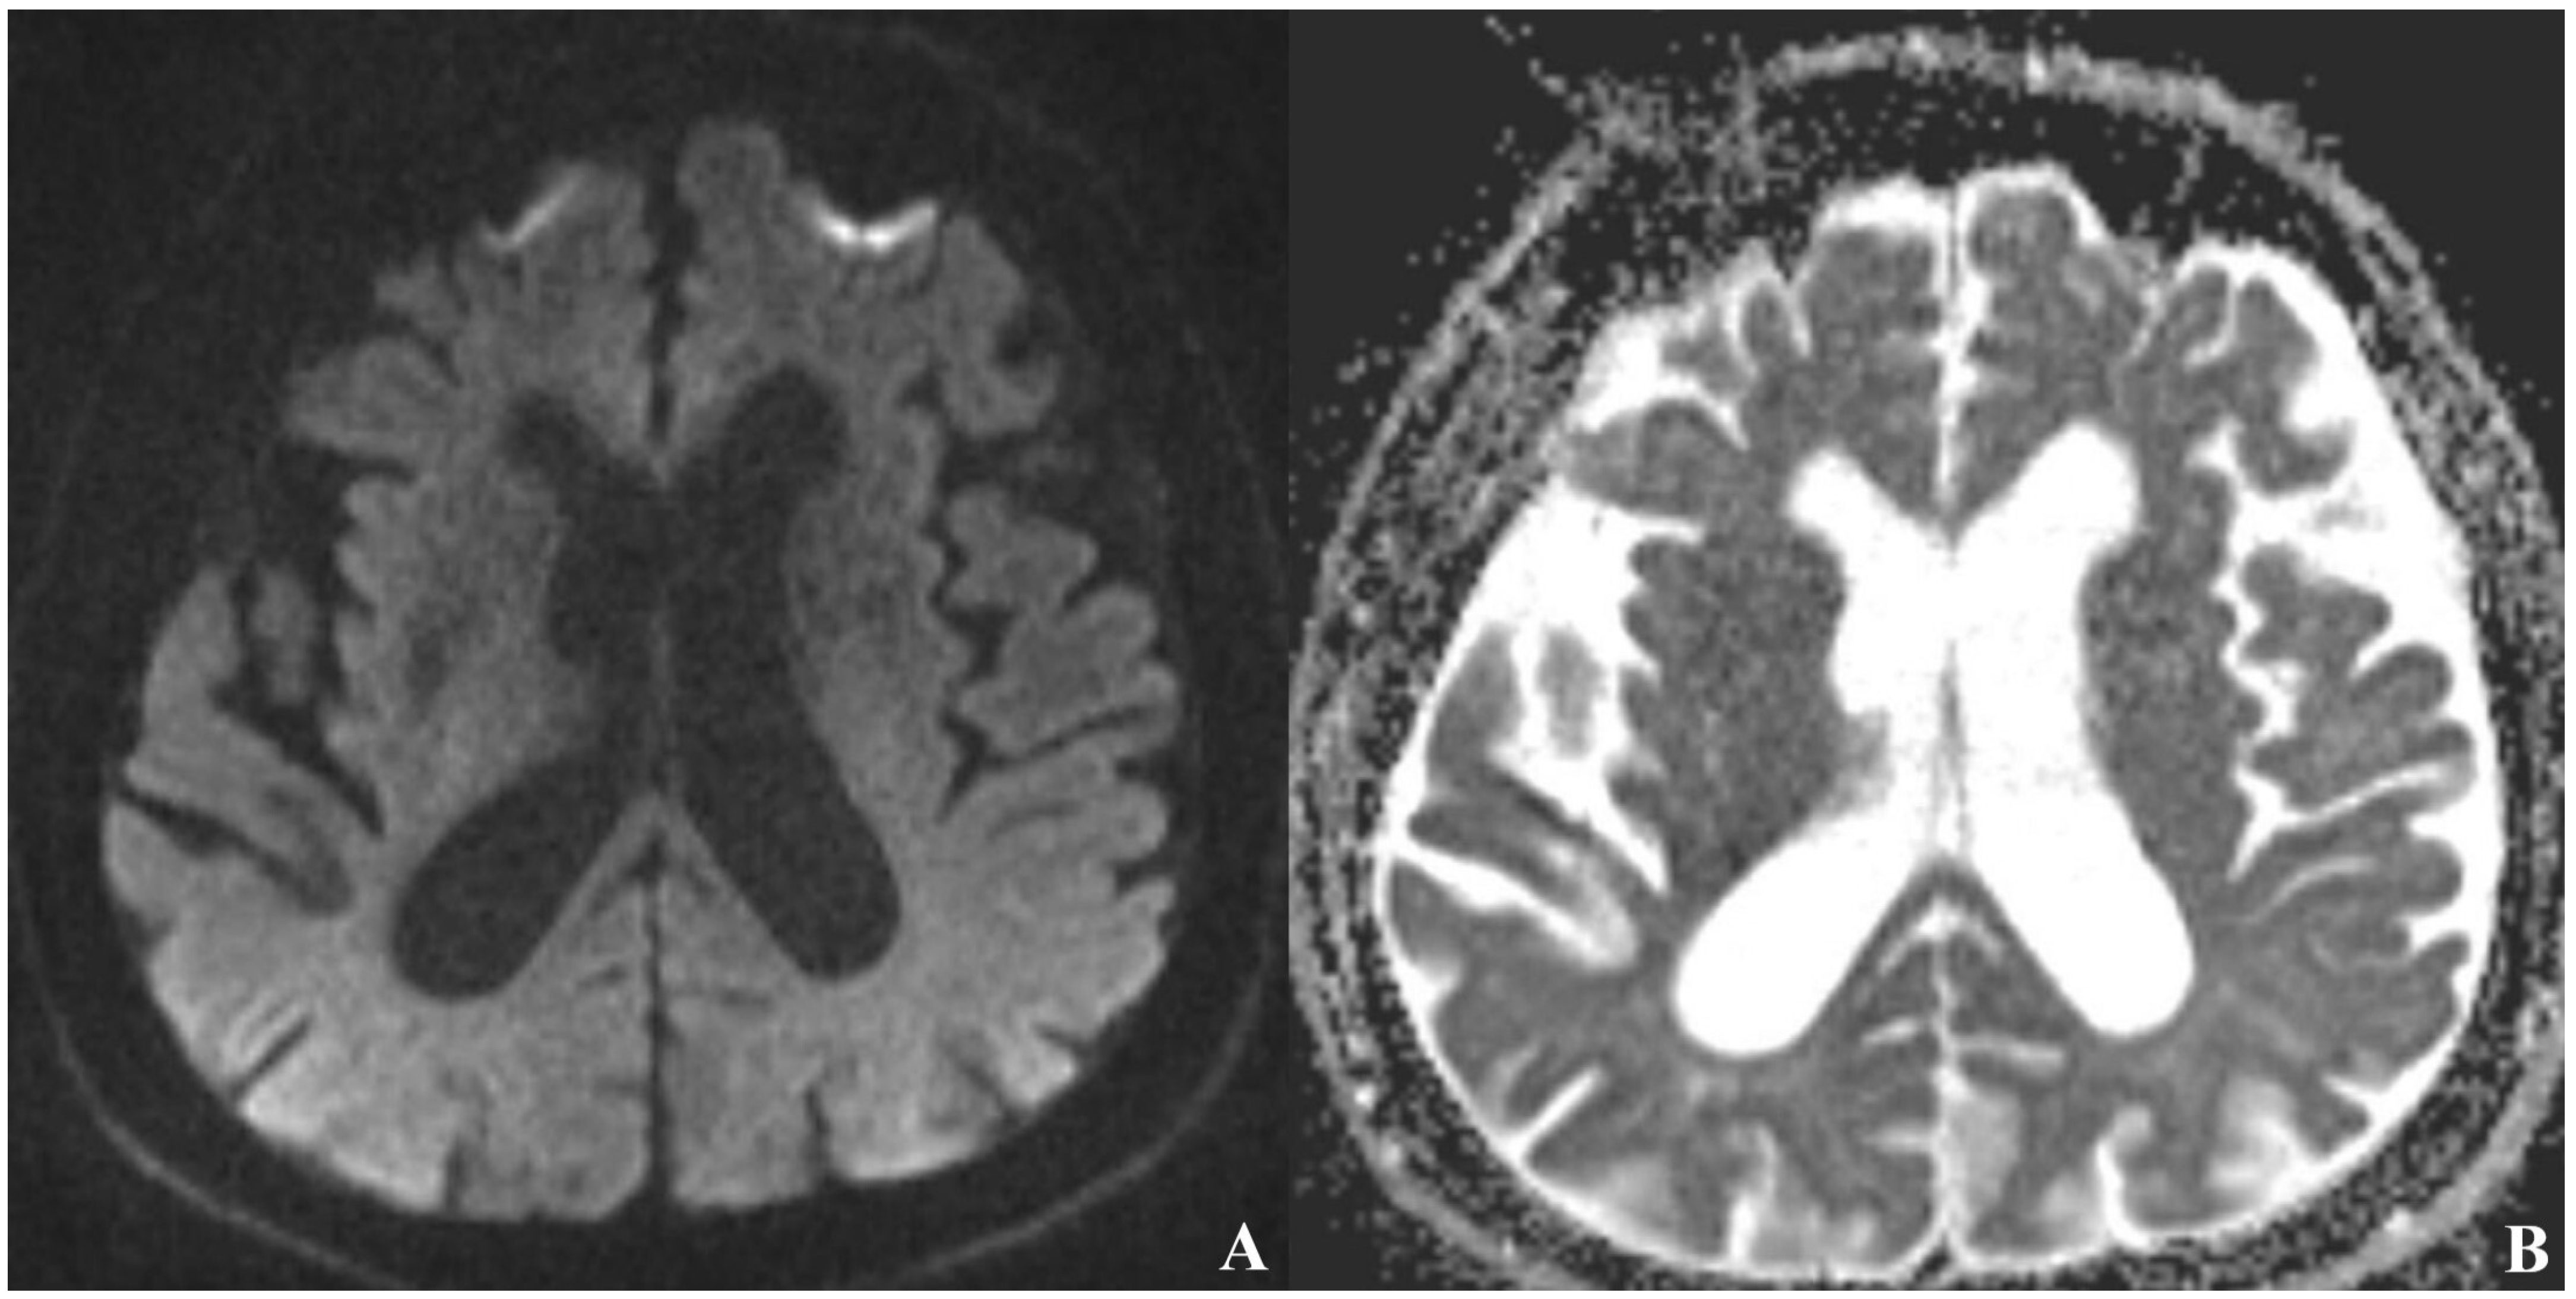

Diffusion-weighted and T2-weighted MRI sequences have shown no pathological findings apart from age-related diffuse cerebral atrophy (Figure 4).

Figure 4.

No evidence of ischemia in the left hemisphere on diffusion-weighted MRI [(A) DWI, (B) ADC map sequence].